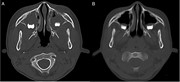

Stage IV sporadic Burkitt's leukaemia with osteolysis in the maxillary sinuses

Yohsuke Yoshioka and others

Journal of Surgical Case Reports, Volume 2016, Issue 2, February 2016, rjw011, https://doi.org/10.1093/jscr/rjw011